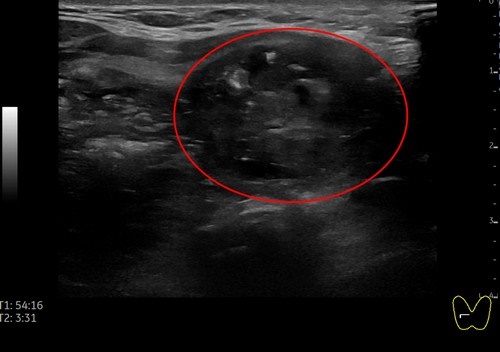

日前,一位51歲女性病人因頸部中間部位腫大來花蓮慈濟醫院影像醫學部施于泰醫師門診,經以超音波檢查,發現右邊有一5.15公分結節,另一個結節靠近甲狀腺峽部約2.99公分;在以細胞學穿刺檢查後為良性結節。病人在接受甲狀腺消融術治療後,隔天即出院恢復正常生活,且一週後已明顯消腫,無副作用發生。

右圖:女病患右側甲狀腺5.15公分結節微波消融後超音波影像。(施于泰提供)